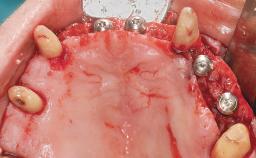

Conventional Loading of Eight Implants in the Maxilla and Final Restoration with a Full-Arch Gold-Ceramic FDP

A 35-year-old Caucasian female presenting with advanced periodontal disease involving both the maxillary and the mandibular dentition was referred for evaluation. The patient, a non-smoker in good general health, requested treatment for recurrent periodontal abscesses, tooth mobility, and discomfort during chewing, as well as restoration of her missing teeth with a fixed prosthesis to improve mastication and esthetics. All residual maxillary teeth exhibited plaque deposits, deep pockets, bleeding on probing, and class III mobility and were evaluated as hopeless. All residual mandibular teeth except tooth 37 could be maintained after periodontal therapy.

Bone Augmentation Horizontal|Staged|Vertical

Augmentation Materials Autogenous block(s)

Soft Tissue Grafting Staged